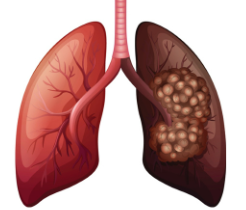

폐암 이란?

폐암은 말 그대로 폐에 생긴 악성종양을 의미합니다. 크게 소세포폐암과 비소세포폐암으로 나뉘는데, 대부분의 폐암환자분들은 비소세포폐암에 해당됩니다. 전체 폐암 중 80~85%가량 차지하며, 편평 상피세포암, 선암, 대세포암등이 속합니다.